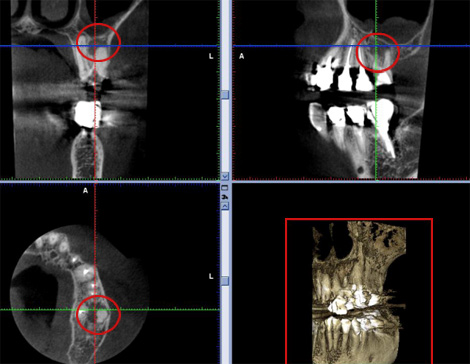

歯科CTを撮影すると頬側(赤丸)の根尖病巣(根の病気)が一目瞭然でわかります。

両者を見比べながら確認することが大切です。